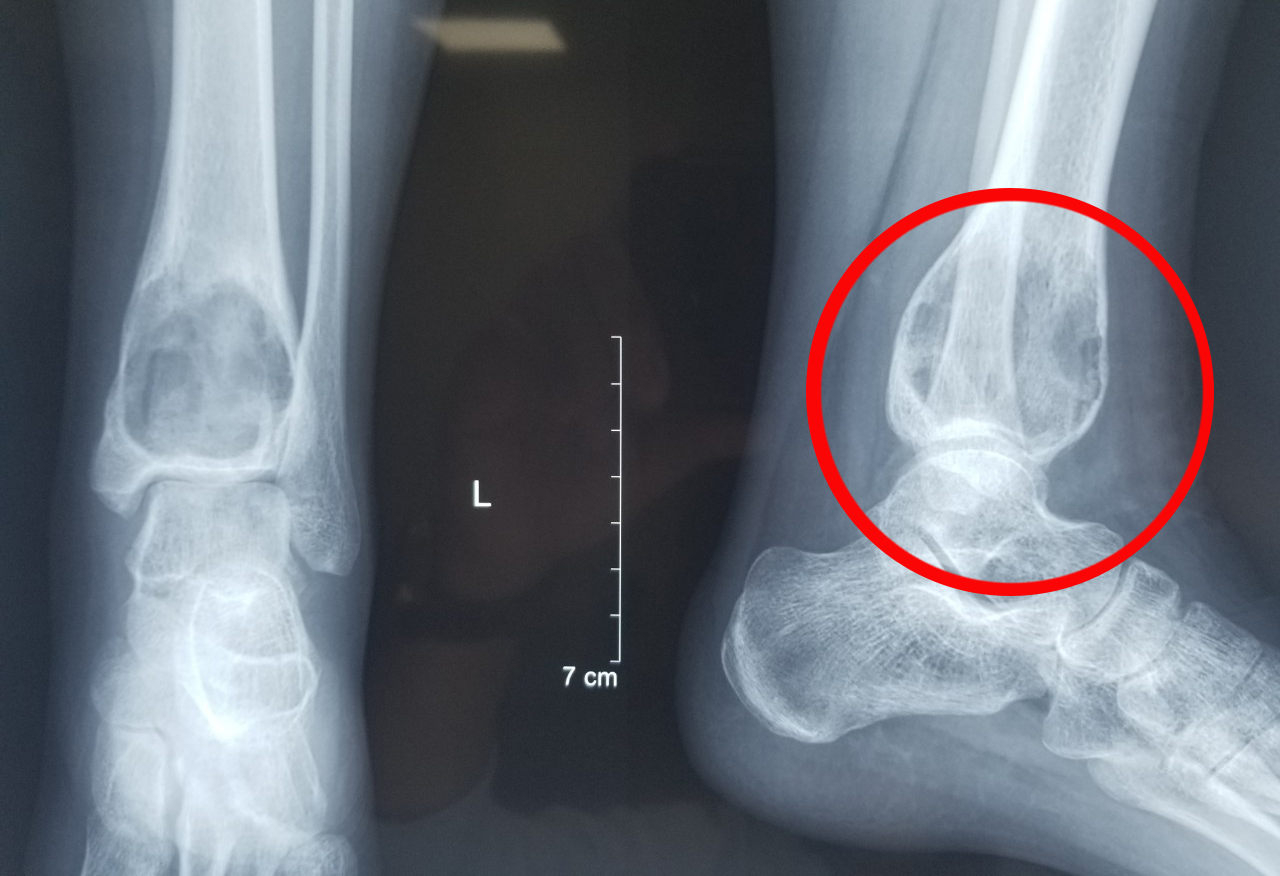

Xương chày có đường kính khoảng 3 cm,trong khi khối u đã phát triển gần 5 cm,làm cho xương căng phình,bề mặt mỏng đi nhiều,khả năng gãy xương rất cao. U đã xâm lấn phần mềm,lan xuống sụn khớp cổ chân. "Nếu không điều trị ngay,u sẽ tiếp tục phát triển,phá hủy bề mặt khớp cổ chân,xâm nhập vào xương ở vị trí này,làm mất chức năng của khớp",bác sĩ Lý nói.

Khối u phát triển gây hủy xương tại đầu dưới xương chày của chị Linh. Ảnh: Bệnh viện Đa khoa Tâm Anh